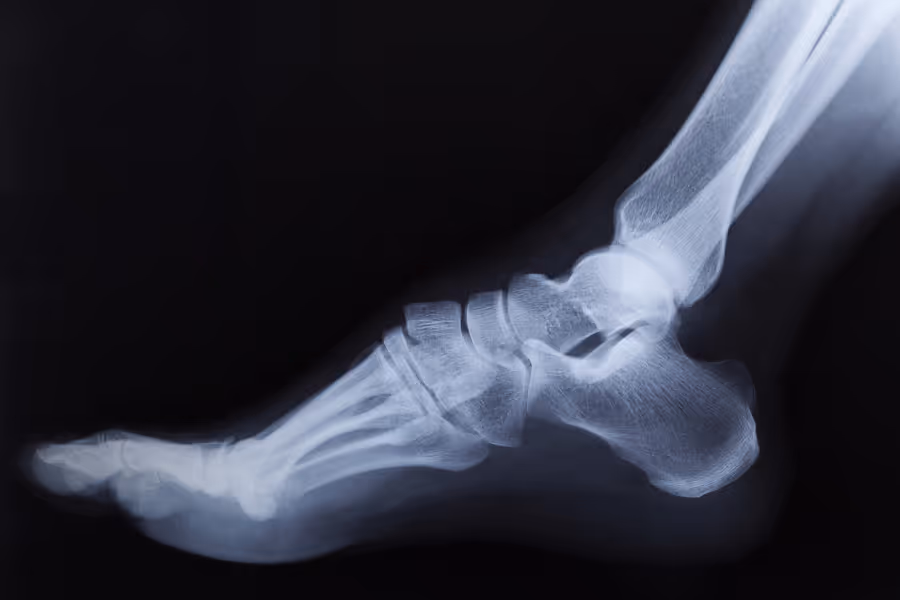

Foot and ankle arthroscopy is a “keyhole” surgery that lets doctors see inside your joint and fix problems using tiny tools.

Instead of a large cut, the surgeon makes a few small incisions and inserts a pencil‑thin camera (an arthroscope). The camera shows a magnified, real‑time view on a screen, so the surgeon can precisely work inside the joint.

Through other small portals, the surgeon can remove loose cartilage or bone fragments, smooth rough joint surfaces, shave bone spurs, release tight tissue, or treat inflamed lining (synovitis).

Foot and ankle arthroscopy is a minimally invasive surgery where a surgeon uses a tiny camera and tools to look inside your joint and fix specific problems. It might be right for you if: